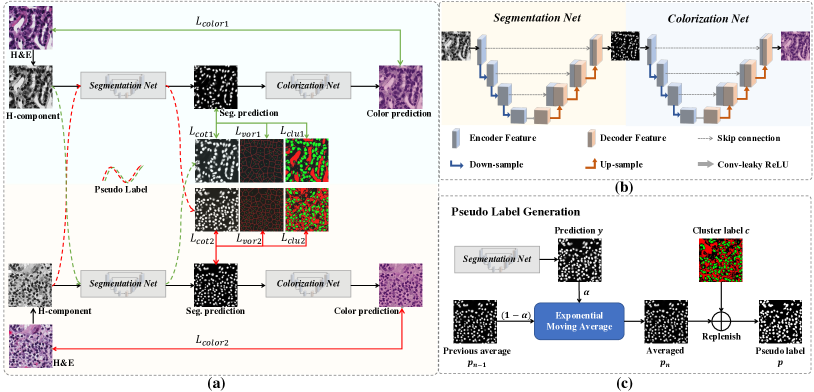

In this paper, we aim at an end-to-end weakly-supervised nuclei segmentation framework based only on point annotations, as illustrated in Fig. 2. The primary idea behind the method is label propagation where the original point labels are propagated to the pixel-level labels in a coarse-to-fine manner. Specifically, the proposed method consists of three parts as follows. First, we convert the point annotations into coarse pixel-level labels by training the initial segmentation network based on the Voronoi diagram and the distance-aware -means clustering algorithm. The coarse pixel-level labels have complementary information with respect to the point labels, while also containing errors and uncertainties. Second, to minimize the distraction caused by the incomplete coarse labels, we design a co-training method, in which a pair of networks supervise each other with the pseudo labels. In this way, the two networks can mutually transfer knowledge to each other and boost the performance. We periodically average the pseudo labels in the training process using EMA to achieve a more stabilized and accurate cross-supervision. Third, to further explore the boundary information which is omitted by the inaccurate coarse labels, we propose a self-supervised representation learning method that transforms H-components into the H&E images. Based on the fact that effective representations are restored in the stain-separated H-components, this nuclei-aware colorization proxy task can extract more details, including the correlation between nuclei and cytoplasm. To this end, a novel end-to-end self-supervised framework is designed, which sequentially combines a Segmentation network with a Colorization network, named SC-Net. The colorization network helps the segmentation network learn to become implicitly self-aware of the nuclei boundaries from the transformation from H-components into H&E images without a need for manual annotations.

In this section, we describe the proposed weakly-supervised nuclei segmentation method using point labels with label propagation, as shown in Fig. 2(a), which consists of three major modules: 1) nuclei segmentation based on coarse pixel-level labels generated from the point labels; 2) a co-training strategy based on exponential moving average (EMA) for generating the pseudo labels, and 3) self-supervised representation learning with H-component based colorization. In the following, we will detail each module.

Using the derived pixel-level coarse labels (i.e., the Voronoi and cluster labels) could potentially achieve reasonable results for nuclei segmentation. In this paper, we adopt the ResUNet [27] as the segmentation network which integrates the residual blocks [52] into the U-Net [10], as shown in Fig. 2(b). The segmentation network is trained with cross-entropy loss with respect to the Voronoi label and the cluster label:

The co-training framework consists of a pair of segmentation networks and , which are trained by two subsets of training data, i.e., and , respectively. To encourage the two networks to learn different and supplementary information from the data, we divide the training set into two non-overlapping subsets of equal size, i.e., and . In the following, we detail the training procedure of the first segmentation network supervised by . The training of the second segmentation network supervised by follows a similar procedure. In the training process of with the subset , besides the aforementioned coarse labels (i.e., Voronoi and cluster), we further utilize the pseudo labels generated by . To stabilize the co-training process, instead of directly using the prediction of another network as the pseudo label [53], we design a pseudo label generation strategy as follows. First, we periodically calculate EMA of the predictions to obtain more robust pseudo labels:

II-C Self-supervised Nuclei-aware Colorization

To exploit nuclei boundary for segmentation network, we design a self-supervised visual representation learning method tailored for nuclei segmentation in pathology images by image colorization based on the H-component. The proposed pipeline consists of two U-Nets in a sequential order, as shown in Fig. 2(b), which first generates the probability map of the nuclei from the H-component image, followed by a colorization network that reconstructs the original H&E image from the probability map. Note that the segmentation procedure can be explicitly trained by the Voronoi label and the cluster label in Eq. (3), as well as the co-training loss in Eq. (7), while the colorization procedure can be trained in an unsupervised manner that converts the H-components to the H&E stained images. Besides, the segmentation network and the colorization network are connected by the probability map of the nuclei, which achieves an end-to-end training and the colorization task would implicitly promote the nuclei representation learning of the segmentation network. The colorization loss is computed between the predicted and true images as:

To investigate the impact of the proposed co-training and colorization methods, we validate the effectiveness of each module on the MoNuSeg dataset. Considering that Voronoi labels provide more shape supervision information than point annotation, we regard the model that jointly uses the point annotation and the Voronoi label as the baseline, and mainly evaluate the improvement of each module upon this baseline in Table III. Model A utilizes only point annotation and Voronoi labels with cross-entropy loss. For a fair comparison with co-training, we employ two separate models which have the same architectures for co-training and average the predictions of the two models in inference. Model B further adopts the cluster label. It can be seen that the cluster loss is beneficial in segmenting overlapping nuclei, improving the from 60.20% to 72.48% and the AJI from 43.01% to 51.77%, which indicates that simply using the point annotation and the derived Voronoi labels cannot provide sufficient supervision for the nuclei segmentation due to the lack of boundary and area information. However, the cluster labels generated by the -means algorithm cannot separate close nuclei which would introduce distraction to the training process, as shown in Fig. 1. To address this challenge, Model C utilizes the co-training strategy that the two models facilitate each other in a bootstrapping way to eliminate the distraction brought by the cluster labels. As expected, co-training brings a consistent improvement in all metrics, including an 1.19% increase to AJI. We believe that co-training compensates for the loss of supervision information in the uncertain regions in the cluster label, and the probability map with EMA by another model provides more precise and robust supervision in the nuclei boundary. Visualization of the segmentation results can be found in Fig. 3, and it can be seen that with the co-training strategy, the model can achieve more accurate results, especially in the nuclei boundary area. Model D involves colorization as a proxy task to implicitly learn to be self-aware of the nuclei boundary. Instead of directly coloring the H-component (Fig. 4(a)) to the H&E map (Fig. 4(d)), we use the segmentation probability map (Fig. 4(b)) as the input of the colorization network, which can help us to boost the segmentation accuracy. The experimental result shows that integrating the colorization tasks could not only improve the by 1.54% and AJI by 3.24%, but also promote Acc by 0.18% without dropping F1 score, proving that the colorization task has a significant guiding effect on nuclei segmentation. In Fig. 4(c), the improvement of colorization in the nuclei boundary area can also be observed. In general, the four modules used in our method have complementary advantages. By minimizing the weighted sum of the four losses, the proposed framework can distinguish between nuclear and non-nuclear to the greatest extent.